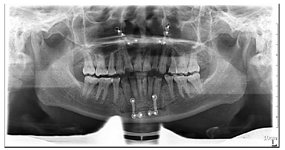

(1)面部检查:面部外形不对称,颏部居中,两侧口角高度不一致,面下1/3高度减小,两侧颧弓突度一致,下颌前突。中位笑线,上唇长度适中(图1)。(2)关节检查:颞颌关节:弹响(-),杂音(-),疼痛(-)。开口度正常,开口型有偏斜,肌肉触诊压痛:右侧上颌结节(+)、左侧上颌结节(++)、双侧翼内肌(+),其他肌肉及颞下颌关节区未诉异常,关节载荷实验无任何紧张和疼痛不适。(3)口内检查:上下颌牙中线较面中线向右偏斜,前后牙广泛不均匀磨耗,前牙磨耗后呈刃状;14、21、22、23及下颌牙唇颊侧颈部见釉质缺损,部分牙本质暴露,呈黄褐色,少量白垩色;44牙见开髓孔,表面暂封。12缺失,缺失牙间隙无。全口牙龈色形质未见异常,11牙、21牙唇侧牙龈龈缘高度不一致,21牙较11牙龈缘高约3mm。全口口腔卫生状况良好,菌斑、软垢少量,未及牙石及牙周袋。咬合检查:11-14牙与对颌牙反

,21牙与31、31牙对刃,左侧尖牙至前磨牙深覆盖,

曲线不平(图2,图3)。(4)影像学检查:

曲面体层片示双侧下颌骨未见明显不对称,牙槽骨未见明显吸收;44牙

面充填物,未见根充物,根尖无明显异常(图4)。CBCT示:双侧髁突形态不对称,左侧髁突表面中央凹陷,余骨质未见异常(图5)。